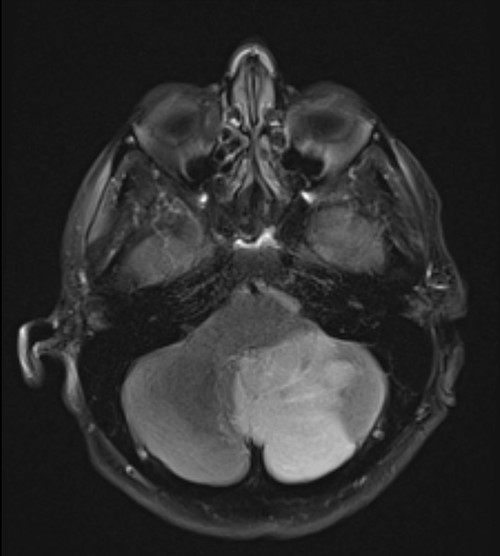

The patient was given an intravenous heparin bolus and transferred to a tertiary vascular centre. At this point, his posterior circulation stroke was not confirmed on imaging although suspected clinically. On review by the vascular team, the patient reported that his left arm symptoms were improving since heparinization. Motor skills, sensation, capillary refill and colour in the limb progressively improved. However, due to persistent dizziness, a magnetic resonance imaging head was performed, which confirmed a large acute left cerebellar infarct (Fig. 2).

T2 sequence magnetic resonance imaging demonstrating large left cerebellar ischaemic stroke.